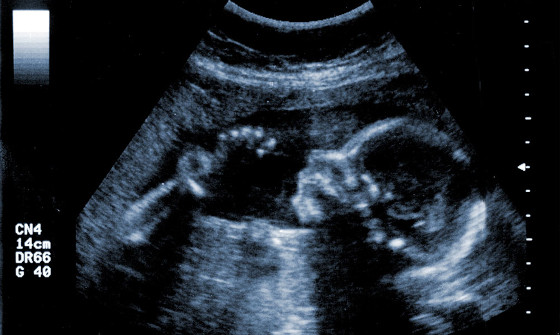

„O capacitate cel puțin curioasă, improprie pentru un organism decedat este cea de a da naștere, existența mamelor aflate în MC reprezentând o serioasă contestație la ideea că persoanele cu acest diagnostic ar fi realmente moarte. (…….) Din păcate, la noi, cei care au absolvit medicina sunt atât de amprentați cu ideea că oamenii aflați în MC sunt morți, încât în momentul în care am povestit la un curs de formare post-universitară, faptul că femei în MC au dus sarcina la o maturitate suficientă a fătului încât să poată produce naștere prin cezariană și copilul să supraviețuiască, au zis că se face asta fiindcă mama e cel mai bun incubator pentru copil, deci din punctul lor de vedere, faptul că un organism poate să nutrească un fetus și să crească sarcina și aceasta să se dezvolte normal, nu era un indiciu clar că femeia respectivă este vie, nu însemna decât că e probabil vreun fel mașinărie care e menținută artificial și nu se stie cum, acest organism «mort», după definițiile actuale care circulă în medicină, naște un copil.”